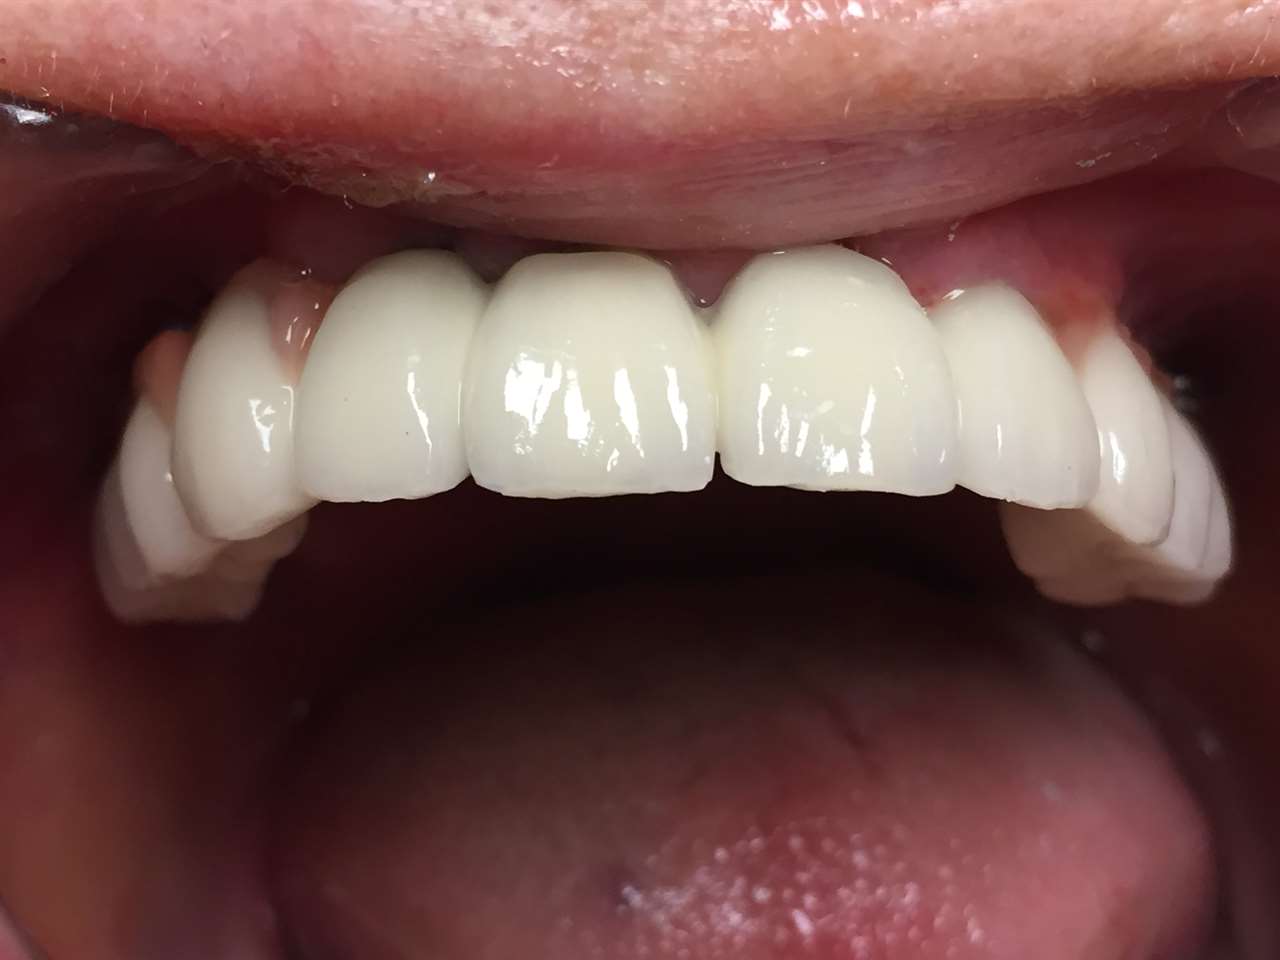

Teljes szájüregi rehabilitáció két lépésben

Ismét egy teljes szájüregi rehabilitáció két lépésben. Először az alsó fogak lettek kihúzva és azonnal implantálva, híddal ellátva, majd később a felső. IHDE svájci azonnal terhelhető implantátumok és cirkónium hidak. Dr. Kelemen Péter és a Symbion Fogtechnika közös munkája.